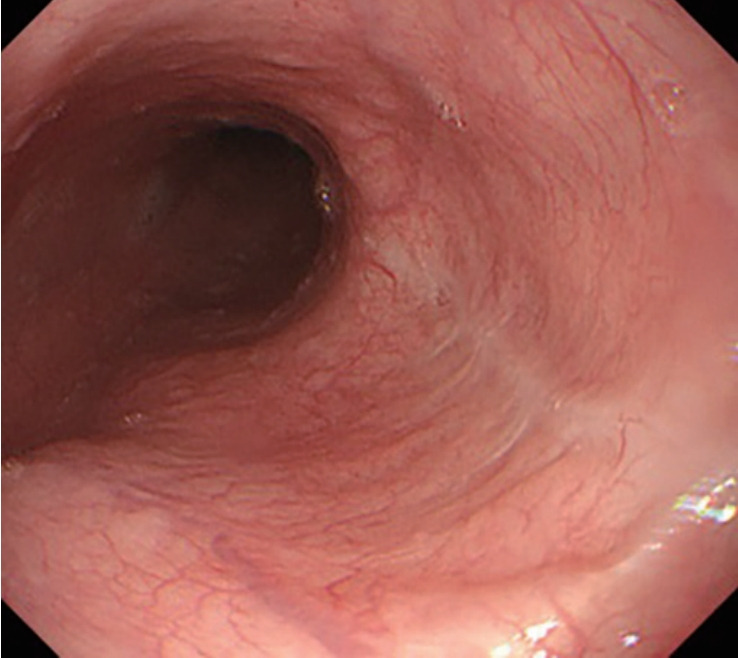

Esophageal Rupture Occurred During the Endoscopic Removal of a Lodged Denture.